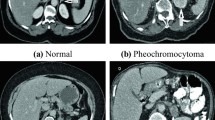

On adrenal glands, benign tumours generally change the hormone equilibrium, and malign tumours usually tend to spread to the nearby tissues and to the organs of the immune system. These features can give a trace about the type of adrenal tumours; however, they cannot be observed all the time. Different tumour types can be confused in terms of having a similar shape, size and intensity features on scans. To support the evaluation process, biopsy process is applied that includes injury and complication risks. In this study, we handle the binary characterisation of adrenal tumours by using dynamic computed tomography images. Concerning this, the usage of one more imaging modalities and biopsy process is wanted to be excluded. The used dataset consists of 8 subtypes of adrenal tumours, and it seemed as the worst-case scenario in which all handicaps are available against tumour classification. Histogram, grey level co-occurrence matrix and wavelet-based features are investigated to reveal the most effective one on the identification of adrenal tumours. Binary classification is proposed utilising four-promising algorithms that have proven oneself on the task of binary-medical pattern classification. For this purpose, optimised neural networks are examined using six dataset inspired by the aforementioned features, and an efficient framework is offered before the use of a biopsy. Accuracy, sensitivity, specificity, and AUC are used to evaluate the performance of classifiers. Consequently, malign/benign characterisation is performed by proposed framework, with success rates of 80.7%, 75%, 82.22% and 78.61% for the metrics, respectively.

• Different types of adrenal tumours can include similar features (i.e., intensity, size, shape), while same-kind tumours can involve different features.